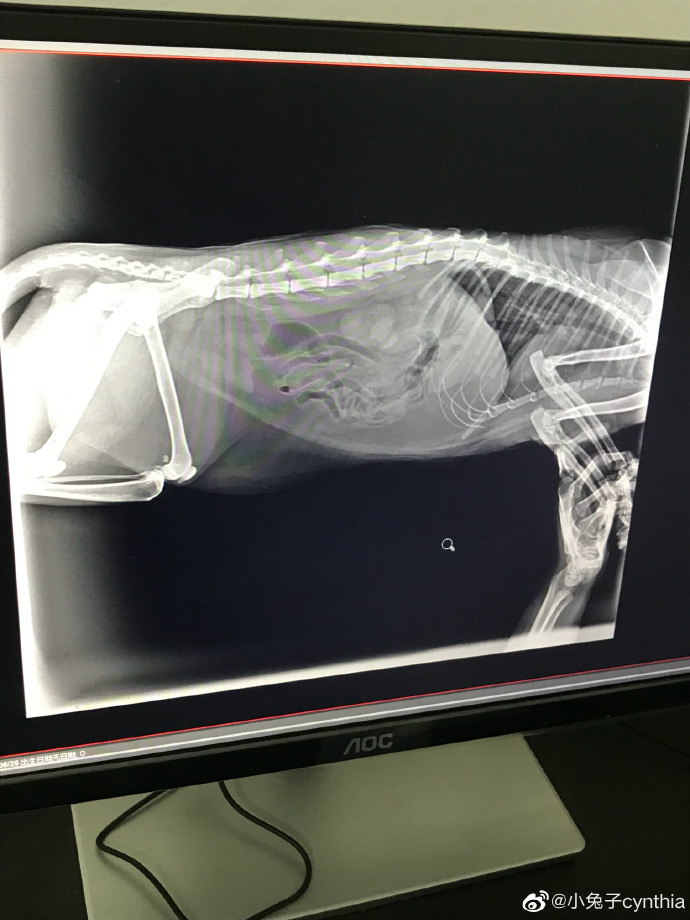

请问猫咪便秘怎么办?已经用过开塞露,猫咪拉了,然后去医院拍了片,医生说肚子里没便便了,开了益生菌,吃了五天,这几天应该没有便便(家里还有一只猫,每天猫砂盆只有一堆便便,以前有两堆),中途喂过一点罐头,但是几天不拉屎不正常,食欲不振,不知道有没有偷偷吃猫粮,求助,谢谢? ...